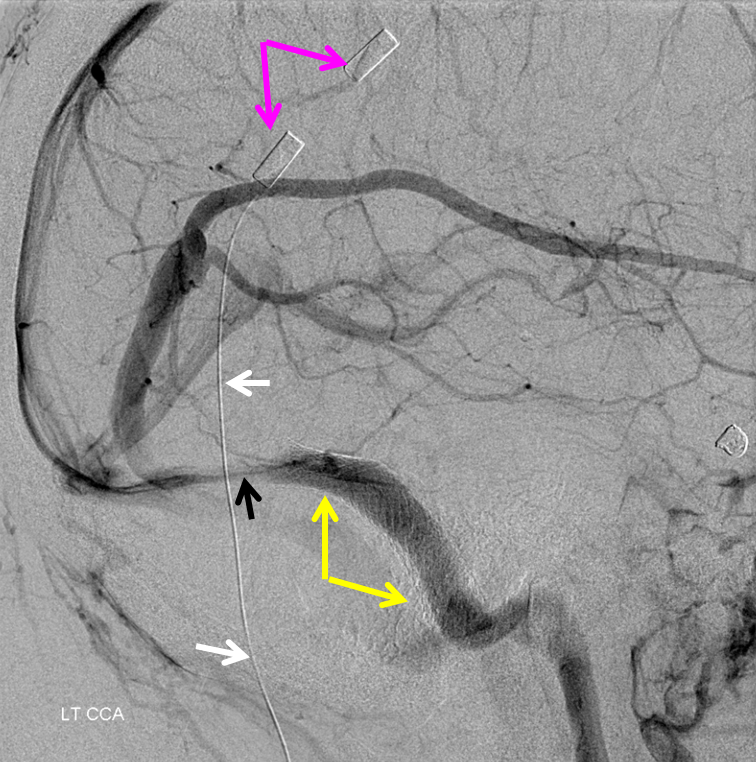

Sagittal Sinus Thrombosis — collaterals.

All of the above anatomic knowledge can become very useful in evaluation of venous thrombosis. Numerous collateral pathways develop in this setting attempting to compensate for the loss. The most dramatic cases usually involve the largest channel — the superior sagittal sinus. In this case, a man presented with what initially was thought to be vasculitis-related brain hemorrhage. Subsequent workup led to an angiogram, where sagittal sinus thrombosis with extensive trans-cerebral and trans-osseous emissary vein collateral channels was seen. In retrospect, these findings were present on the patient’s earlier contrast MRI. “Venovibe” or other contrast-enhanced MR venograms can very sensitive, particularly when interpreted with the appropriate index of suspicion. Noncontrast 2-D time of flight MRV I consider to be next to useless as a problem-solving technique. Any thin-slice postcontrast T1 study is vastly superior.